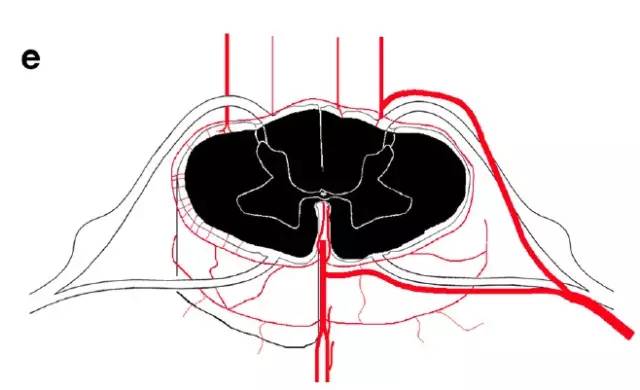

图e,Adamkiewicz动脉闭塞引起的梗死

图f,脊髓前角内外系统之间的分水岭区梗死(蛇眼征)